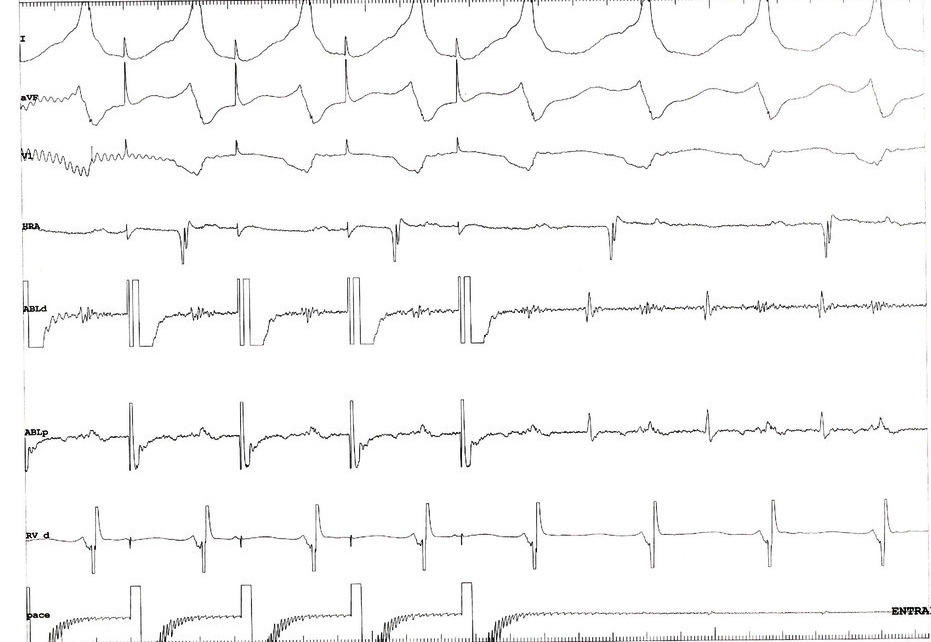

Activation map in RV - Double potentials on septum

rv_dp.jpg

Pacing from site

entrain_rv.jpg

Interpretation

• Diatolic potential is far field

• Captured electrogram is systolic

• Manifest fusion

• PPI = TCL + ~ 35

• What do we do now ?